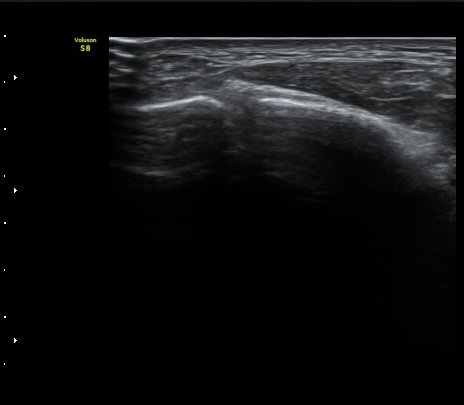

ÃÊÀ½ÆÄ °Ë»ç

Á¾°ñÀÔ¹æ°ñÀδëÀÇ Á¾´Ü¸é°Ë»ç¿¡¼­ ÀδëÀÇ Á¾°ñ ºÎÂøºÎ ÆÄ¿­ÀÌ °üÂûµÊ(»çÁø 1, 2, 3).